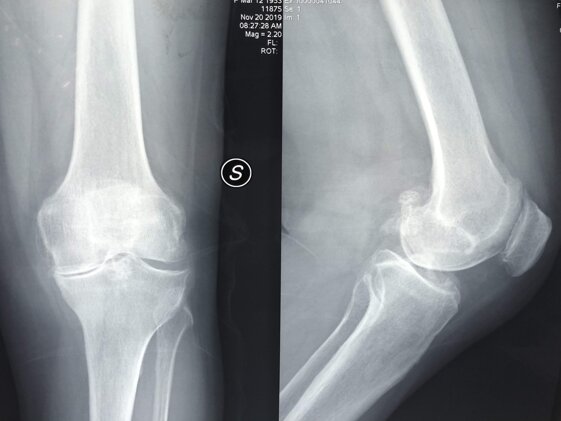

A sinistra radiografie pre-operatorie che evidenziano una grave gonartrosi diffusa con presenza di osteofiti periarticolari e deformità associata (ginocchio varo).

A destra radiografia post-operatoria in AP di intervento chirurgico di Artroprotesi di ginocchio cementata, unico trattamento possibile con pz che presentava dolore continuo e zoppia. Ho utilizzato una protesi con risparmio del legamento crociato posteriore (CR) chiamata Persona  in quanto molto anatomica, cioè rispettante l’anatomia del ginocchio del pz.